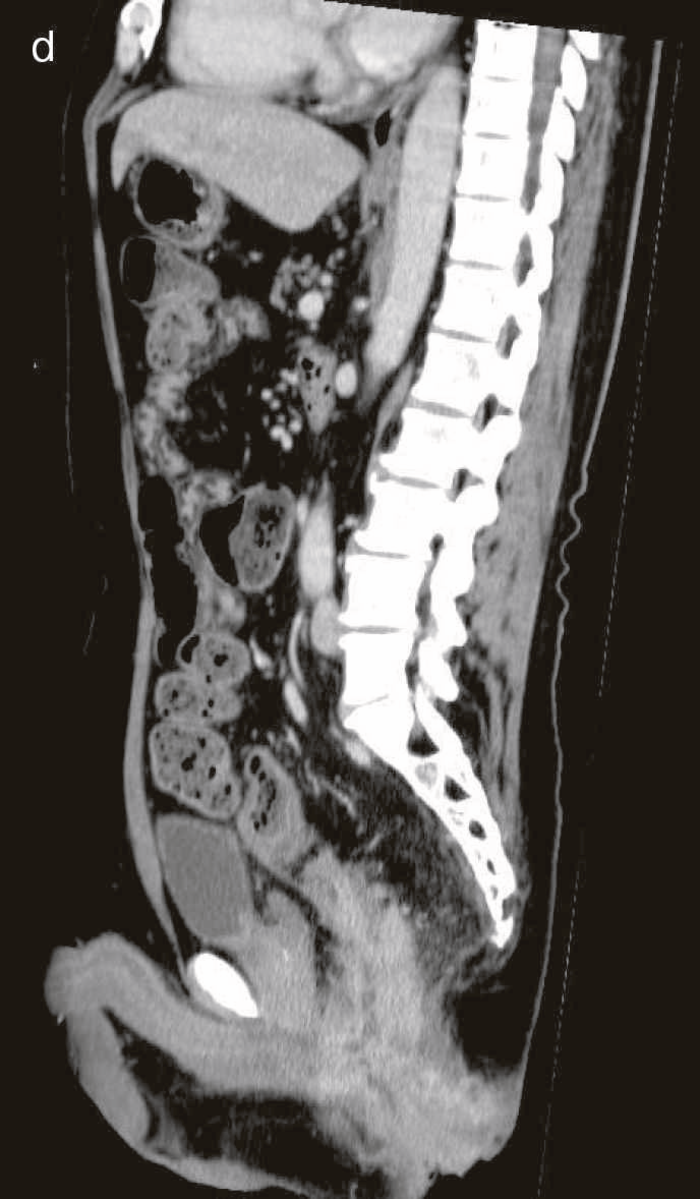

図27 CD直腸肛門部癌の骨盤造影MRI検査像

直腸内に増強効果を受ける分葉状の腫瘤を認める。

診断時のMRIでは直腸下部壁内から周囲にhigh intensity areaが拡がり,右側には痔瘻の瘻管を認めた。high intensity areaは前方で前立腺や陰茎海綿体付近まで広がっていた。

CTではMRIと同様に広範囲のhigh density areaがあり,癌と炎症が波及した領域の区別がつかず右側方領域にリンパ節腫大を認めた。